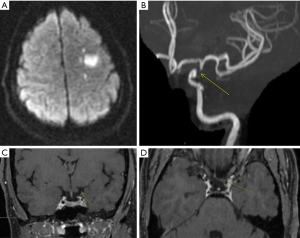

In GCA, VW MRI allows to analyze intracranial arteries (Figure 3) and external branches of the carotid artery, such as the superficial temporal artery, looking for circumferential enhancement. Interestingly, Rhéaume et al. (32) reported in a correlation of imaging and histopathological findings in patients with suspected GCA, that normal findings on scalp artery MRI are very strongly associated with negative temporal artery biopsy findings. This finding suggests that MRI could be used as the initial diagnostic procedure in GCA, with temporal artery biopsy being reserved for patients with abnormal MRI findings. Zeiler et al. (12) showed the post-contrast 3D high resolution VW-MRI can be used to identify inflamed intracranial vascular targets for biopsy, greatly improving the diagnostic accuracy of biopsies for CNSV.